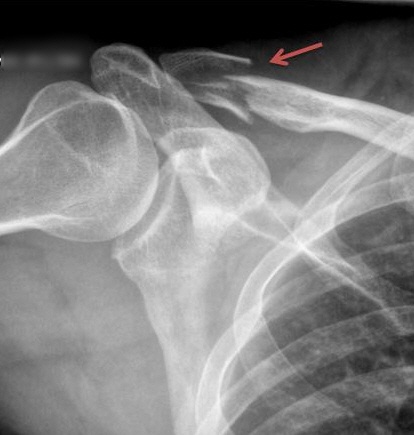

They can also cause a lot of pain inside your body. The picture at right shows my broken right clavicle. Ouch!

You might think of it as the defective output from my bicycling process, which needs improvement.